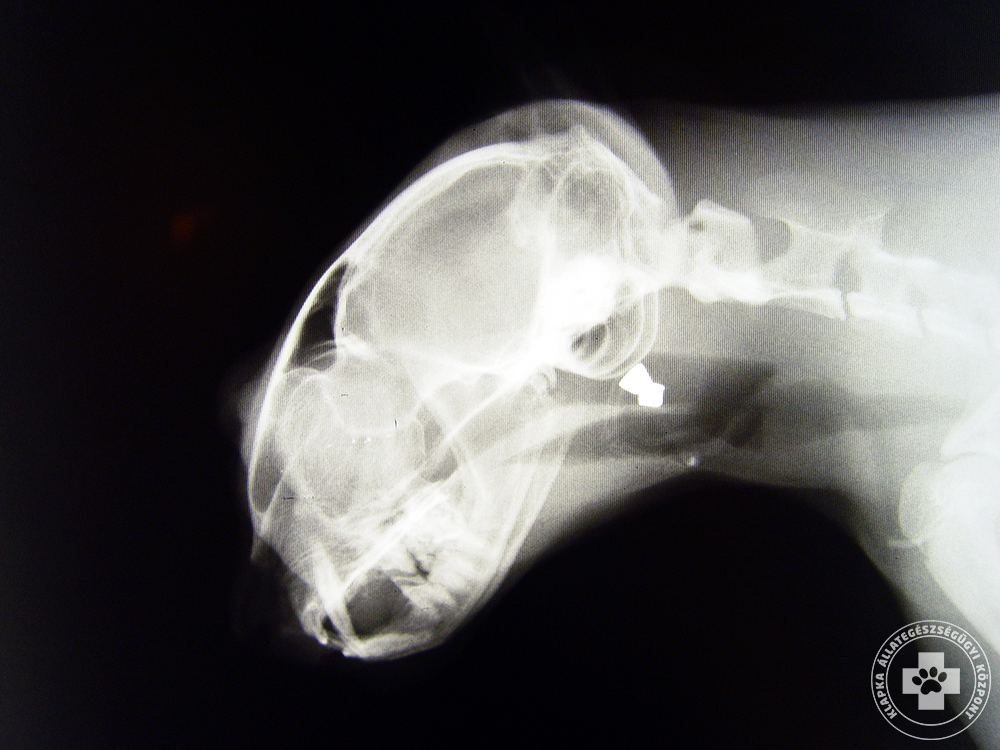

Röntgenvizsgálat (koponya, szemkörnyék)